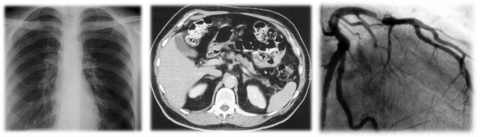

また、近年の目覚ましい画像診断技術の発達や腹腔鏡をはじめとする内視鏡下手術の応用開発を受け、従来の伝統的な系統解剖学の学問体系に「臨床解剖学」の要素を織り交ぜながら、より実践的な解剖学教育を実施しております。